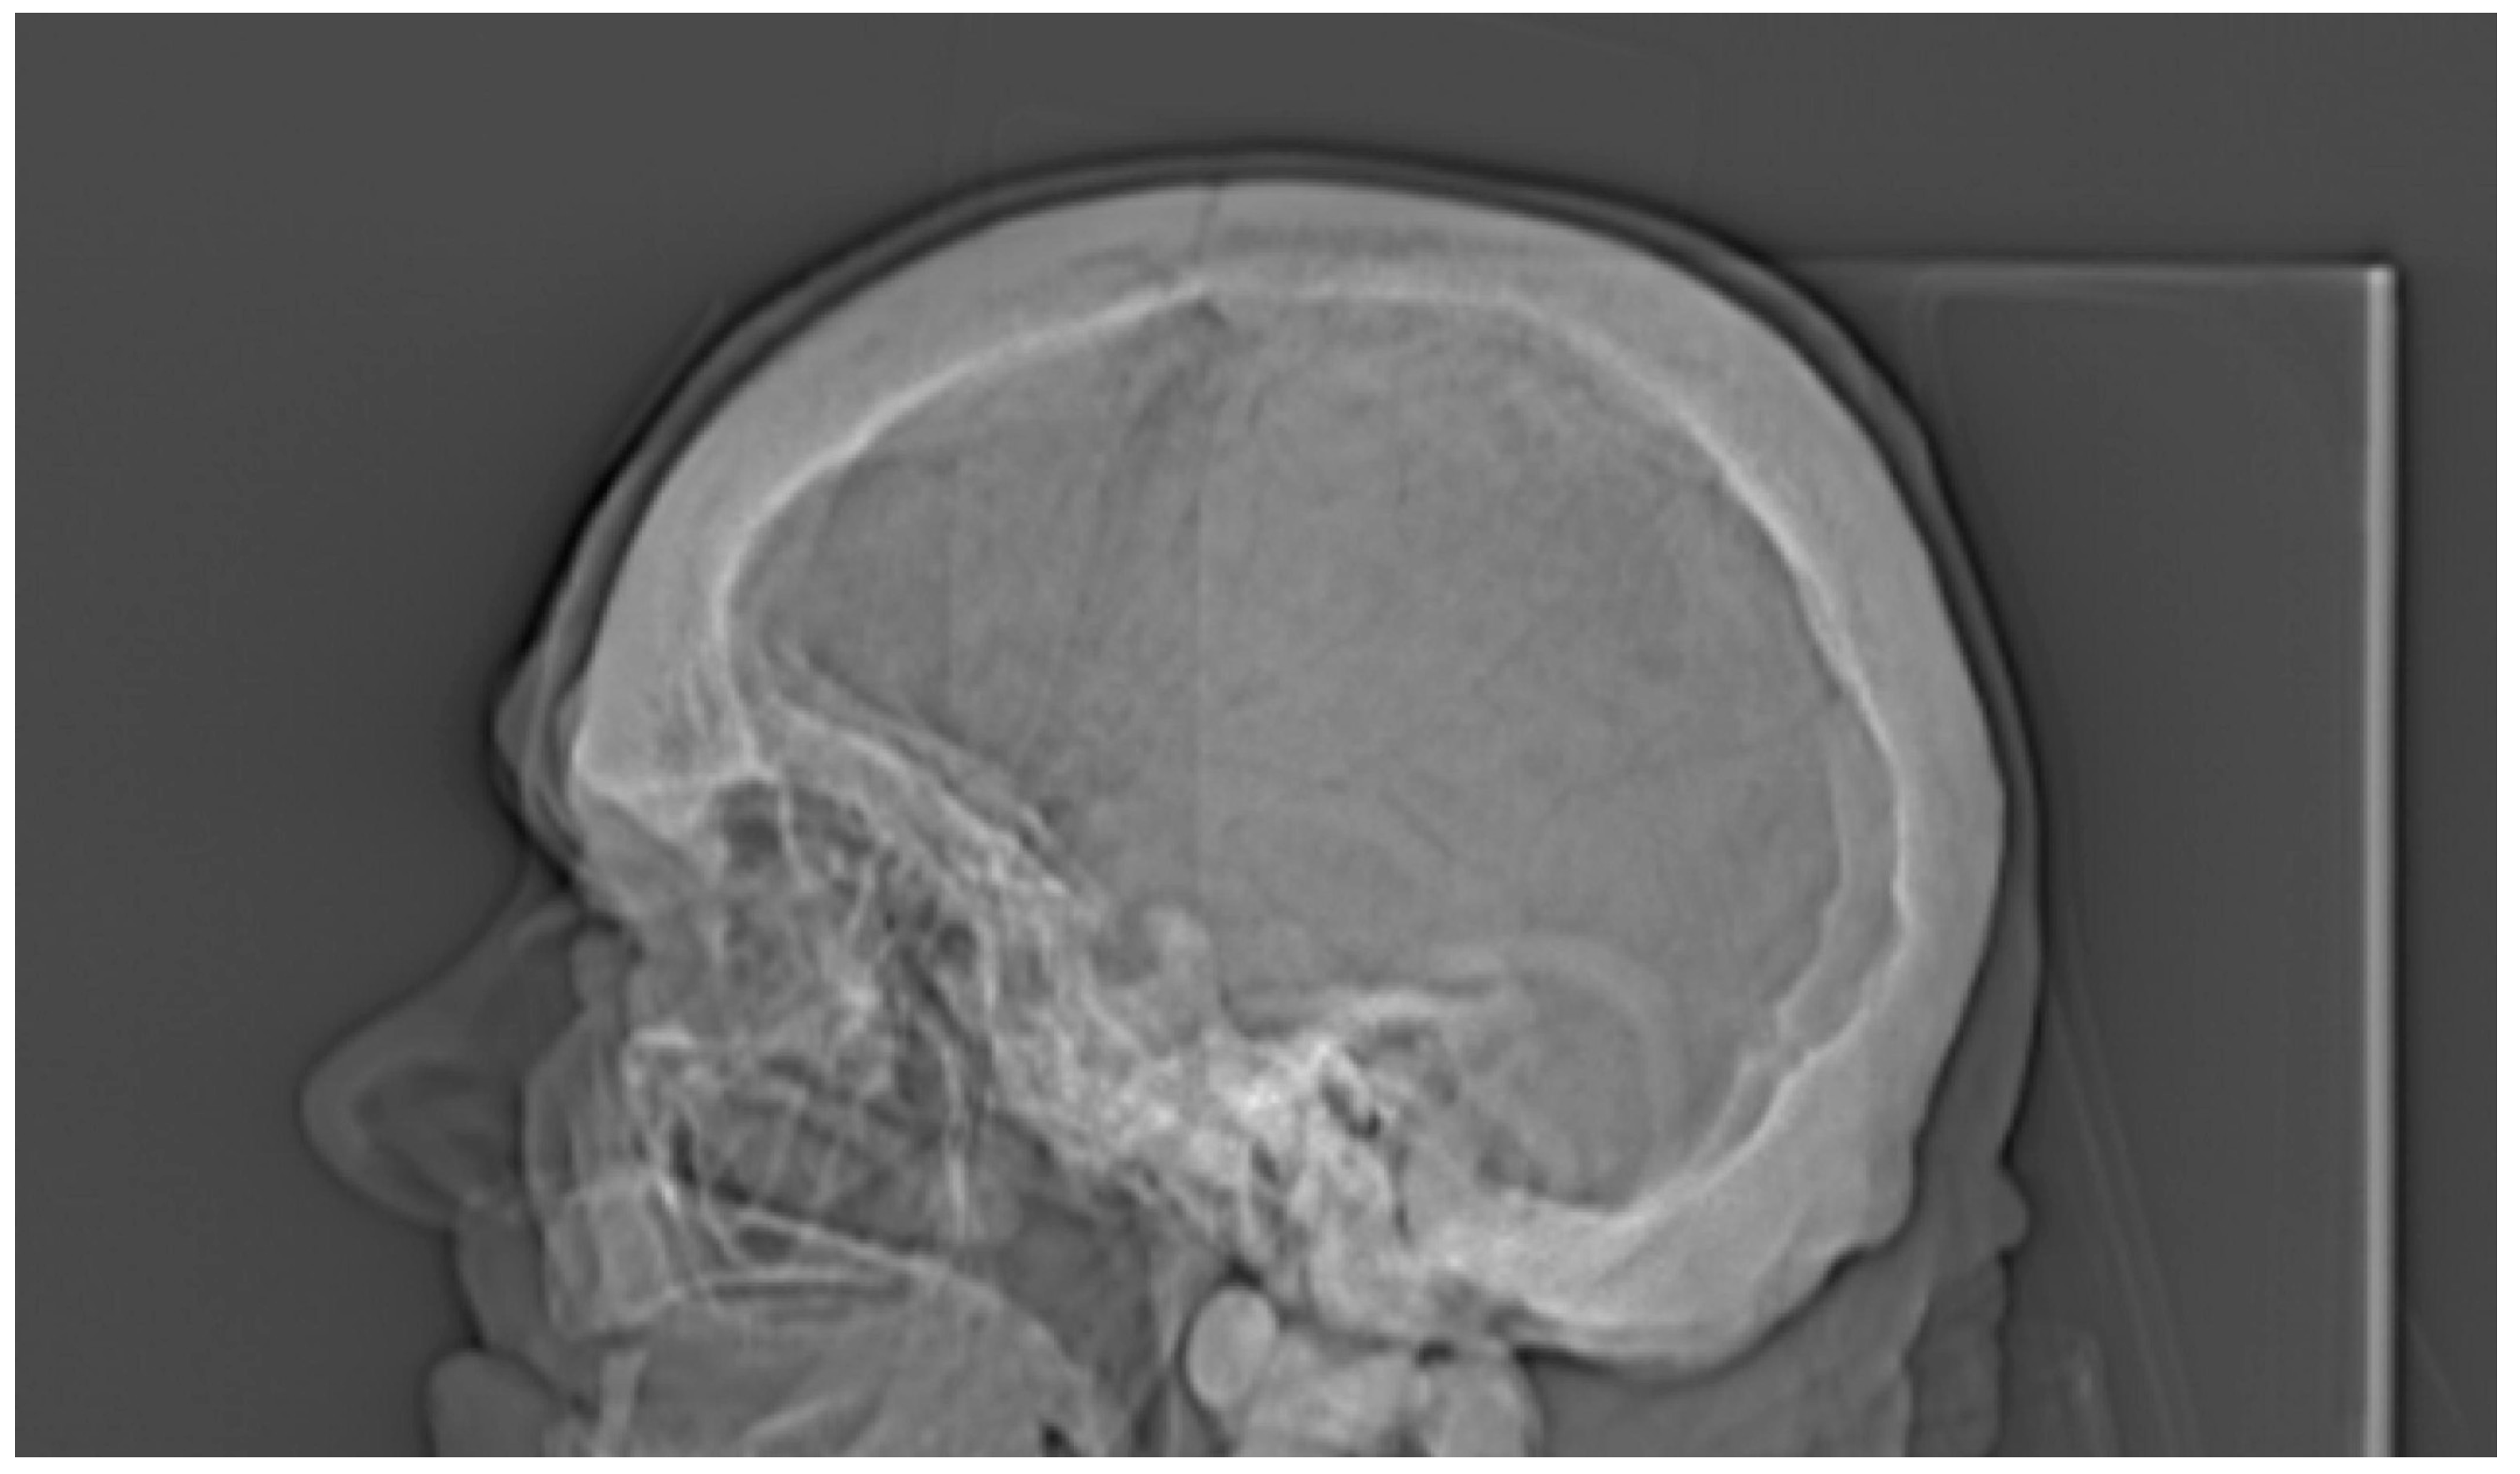

3. Results

| Cranium | |||||

| 50% of cranium height | - | - | - | - | 2.111 |

| General osteosclerosis | + | – | + | + |

| Skull vault osteosclerosis | + | – | + | + |

| Skull base osteosclerosis | – | + | – | + |